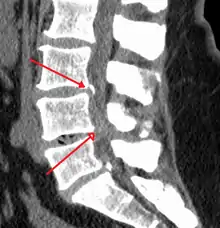

The diagnosis of spinal stenosis involves a complete evaluation of the spine. The process usually begins with a medical history and physical examination. X-ray and MRI scans are typically used to determine the extent and location of the nerve compression.

MRI has become the most frequently used study to diagnose spinal stenosis. The MRI uses electromagnetic signals to produce images of the spine. MRIs are helpful because they show more structures, including nerves, muscles, and ligaments, than seen on X-rays or CT scans. MRIs are helpful at showing exactly what is causing spinal nerve compression.